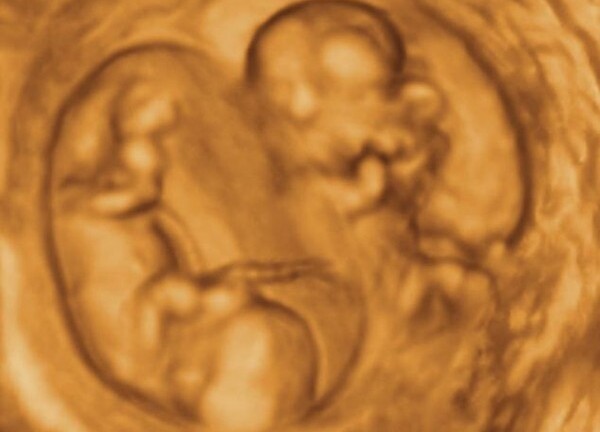

Theo bác sĩ Hoàng Thị Đức, Phó trưởng khoa sơ sinh, chẩn đoán ban đầu cho thấy, cháu được sinh thiếu tháng, rơi trong nhà vệ sinh của một công ty may ở thị xã Bỉm Sơn. Khi nhập viện, miệng bé chảy nhiều máu, hãm lưỡi rách, môi nhợt. Lúc được thở ôxy, bé đã hồng hào trở lại, dù mặt xuất hiện chấn thương nhẹ, cổ ngực có dấu hiệu bầm tím.

Đánh giá tình trạng sức khỏe bé gái, bác sĩ Đức cho hay, bệnh nhân có nguy cơ tử vong rất cao nếu không được cấp cứu kịp thời. Sau 3 ngày được đưa đến bệnh viện, tuy sức khỏe đã ổn định song bé vẫn phải nằm trong lồng kính, ở khu vực cách ly đặc biệt.